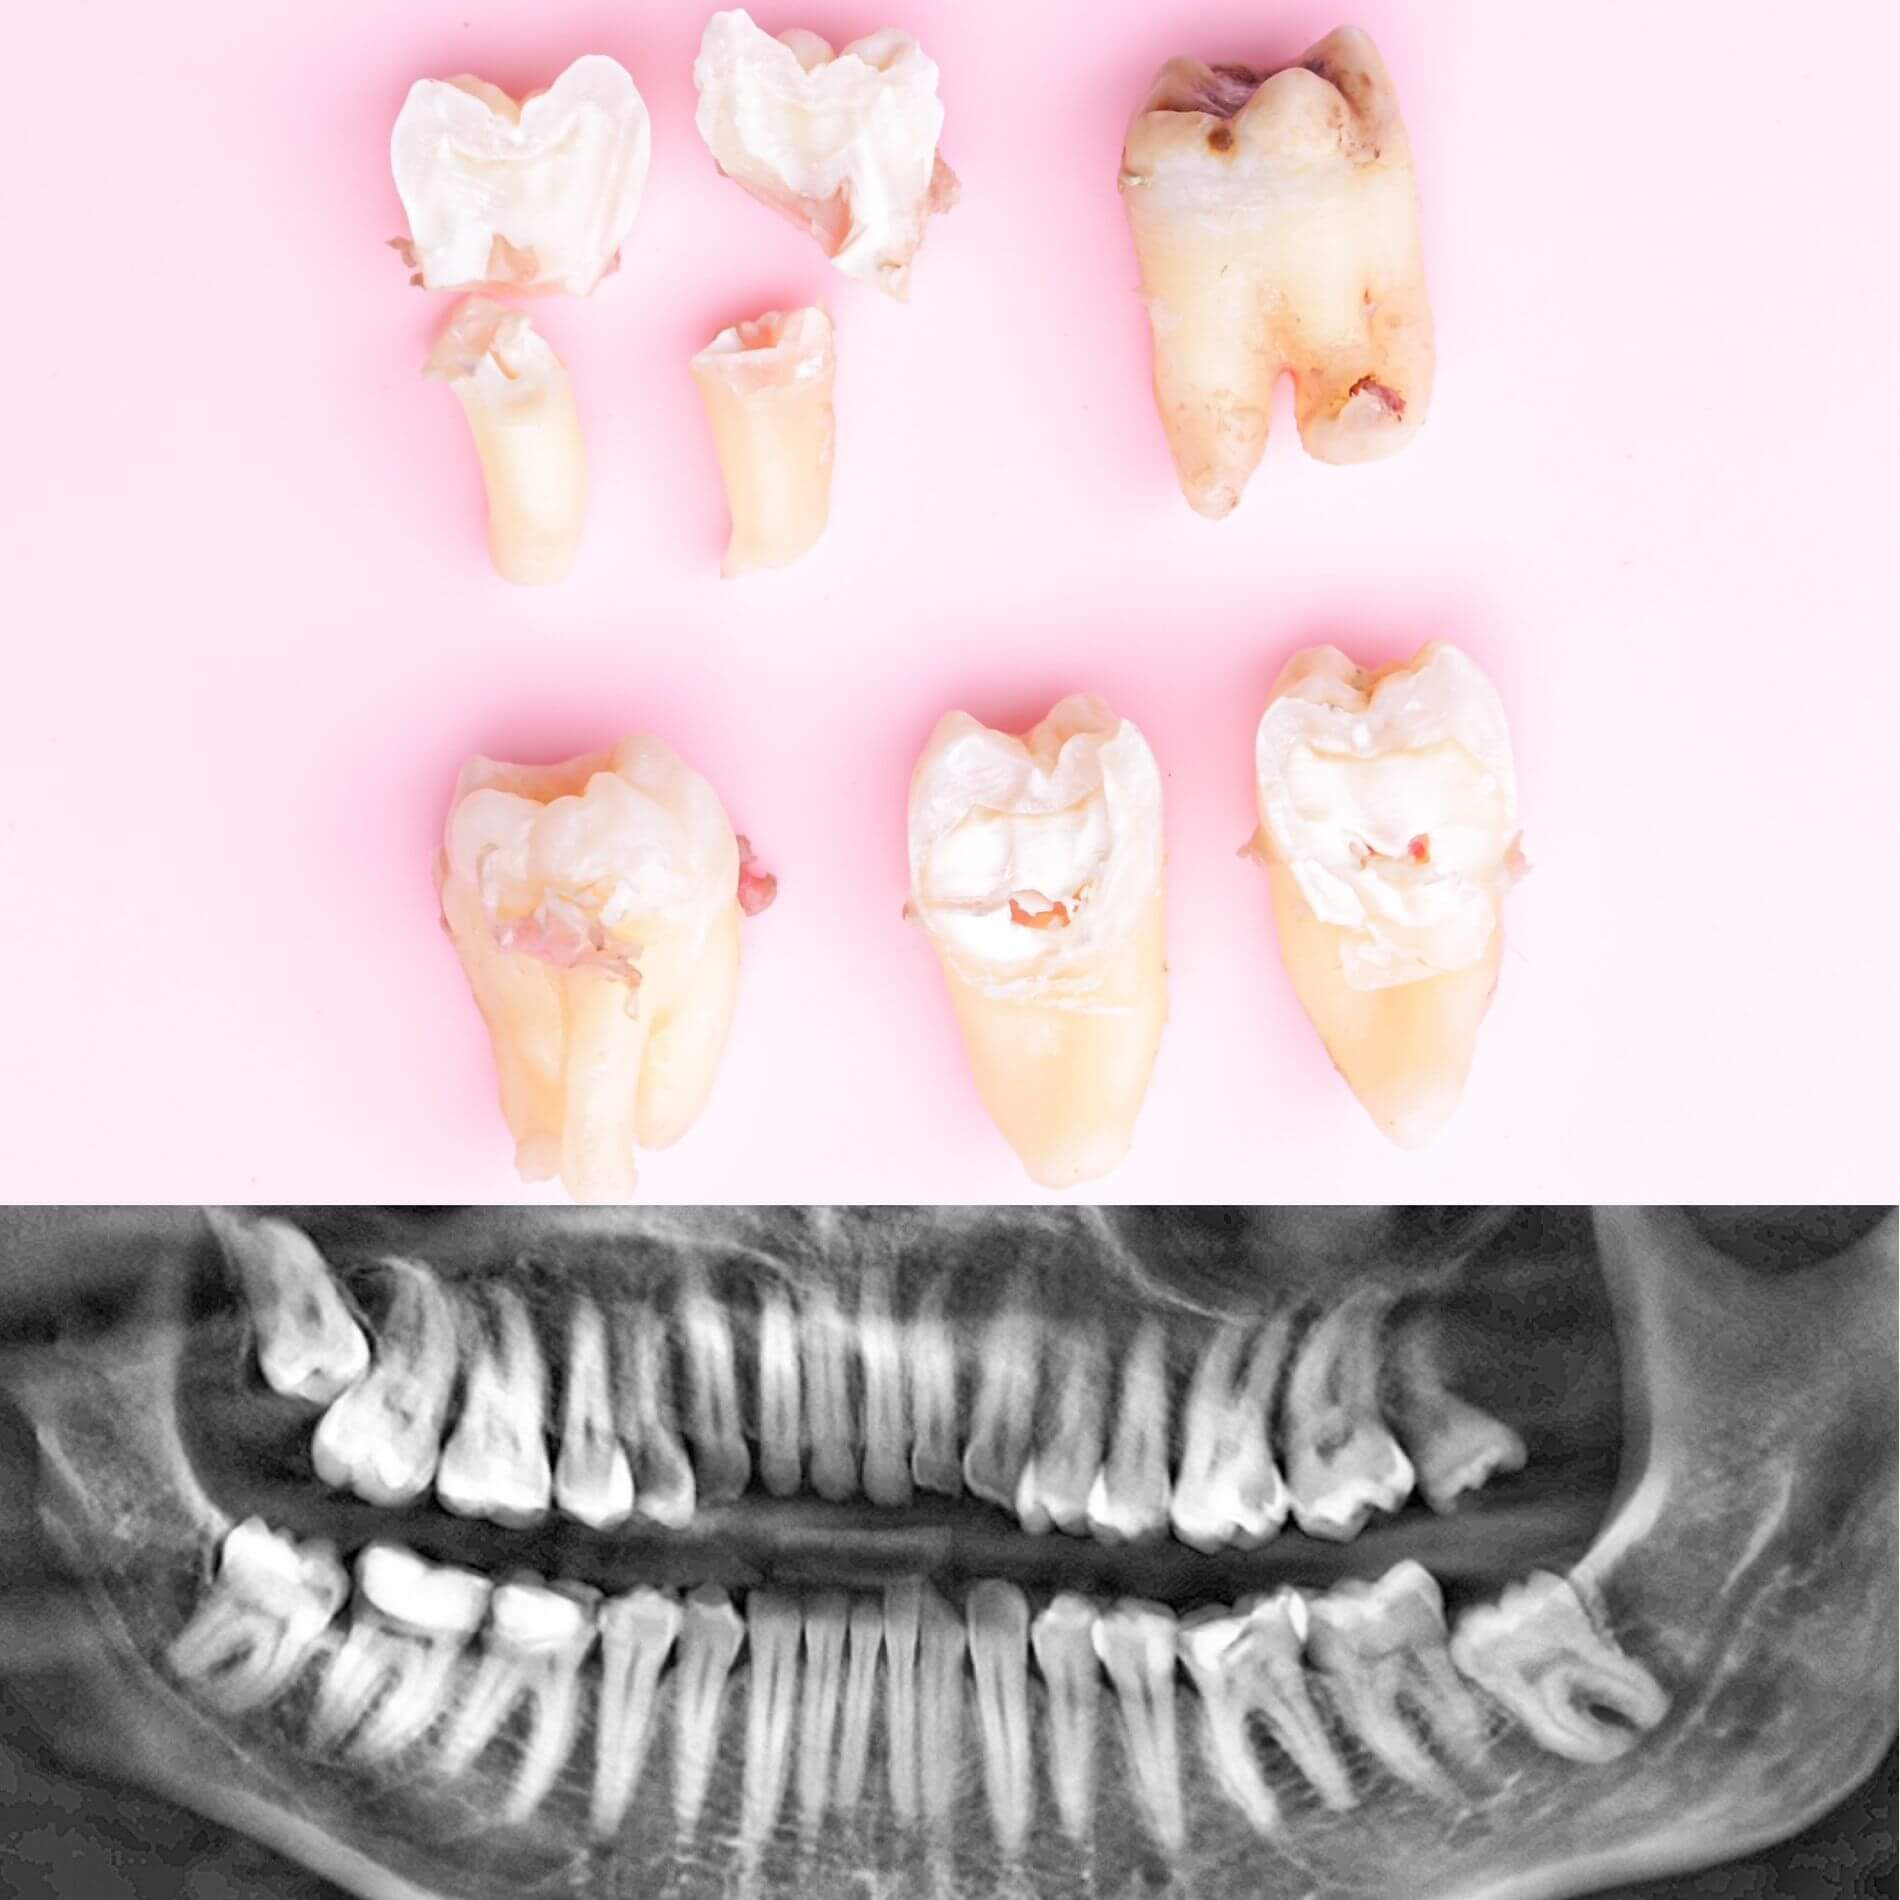

Виды удаления зубов мудрости

• Полное удаление зуба - если зуб полностью прорезался и имеет сросшиеся корни.

• Отдельное удаление коронки зуба и его корней - если зуб прорезан и корни растут по отдельности.

• Удаление зуба по схеме 1 или 2 с разрезом десен - если зуб прорезан частично.

• Разрез десен, освобождение зуба от близлежащей кости ультразвуком и удаление по схеме 1 или 2 - если зуб не прорезался, но беспокоит.

Вырвать зуб мудрости во Львове можно проще, чем тебе кажется, в Космической стоматологии Драганчука. Начни этот путь с простого шага - первичной встречи с хирургом-стоматологом. На консультации мы сделаем основное - направим тебя на 3D компьютерную томографию, чтобы учесть близость нижнечелюстного нерва (нижние 8-ки) и верхнечелюстной пазухи (верхние 8-ки) и составим план удаления зубов.

Галерея